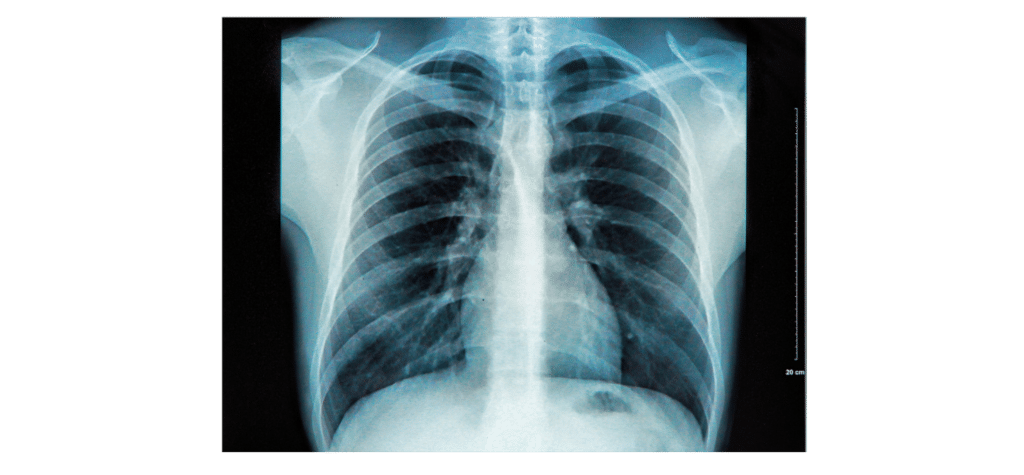

• X-ray Imaging – X-rays mostly pass through soft tissue such as muscle and fat but they are absorbed by denser materials like bones. This means if we take a picture of the body using X-rays, we can see the what the bones look like inside the body.

Question 2: A patient is having a chest X-ray where X-rays are aimed at the patient and detected on the other side of them. Explain why an X-ray image shows the patient’s bones.

X-rays are absorbed by dense materials such as bone.

X-rays pass through less dense materials such as muscle and fat.